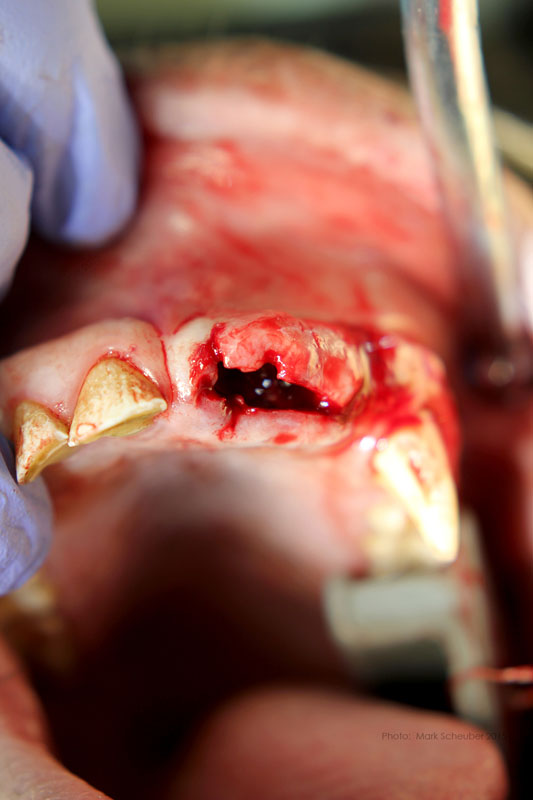

Incision on crest of ridge.

556 surgical bur used to remove approximately 2mm. of alveolar bone surrounding each root ("ditching".)

Luxator technique utilized to remove residual roots.